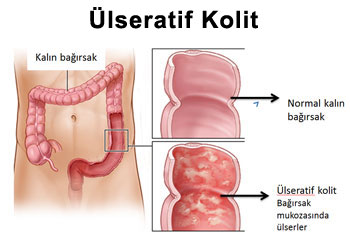

Gýdalarýn, aðýzdan sonra vücudumuz içindeki seyri sindirim kanalýnda olur. Ýltihabi b.. Detay

Gýdalarýn aðýzdan alýnmasýndan sonra vücudumuz içindeki, sindirim kanalýnda yol alýr... Detay